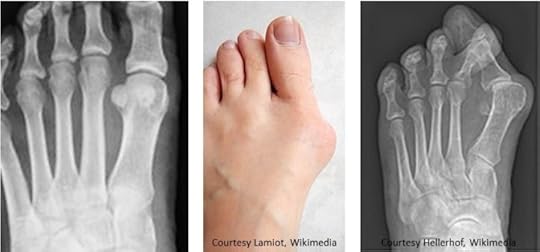

Left: normal alignment Center and Right: laterally deviated big toeFirst, what is a bunion? Known in medicalese as hallux valgus, it is a deviation of the big toe (hallux in Latin). Rather than pointing straight ahead, the big toe points toward the outside of the foot. Accompanying the angular deformity is a large bump in the inside of the foot at the base of the big toe. In extreme cases, the big toe angles sufficiently that it overlaps the second or even the third toe. Genetics, variations in alignment of adjacent bones, and muscle imbalance can predispose an individual to hallux valgus, but the most common cause is wearing pointy-tipped shoes that unnaturally scrunch the toes together and push the big toe to the side. In medieval times, Crakows were culprits. Louboutin’s are today.